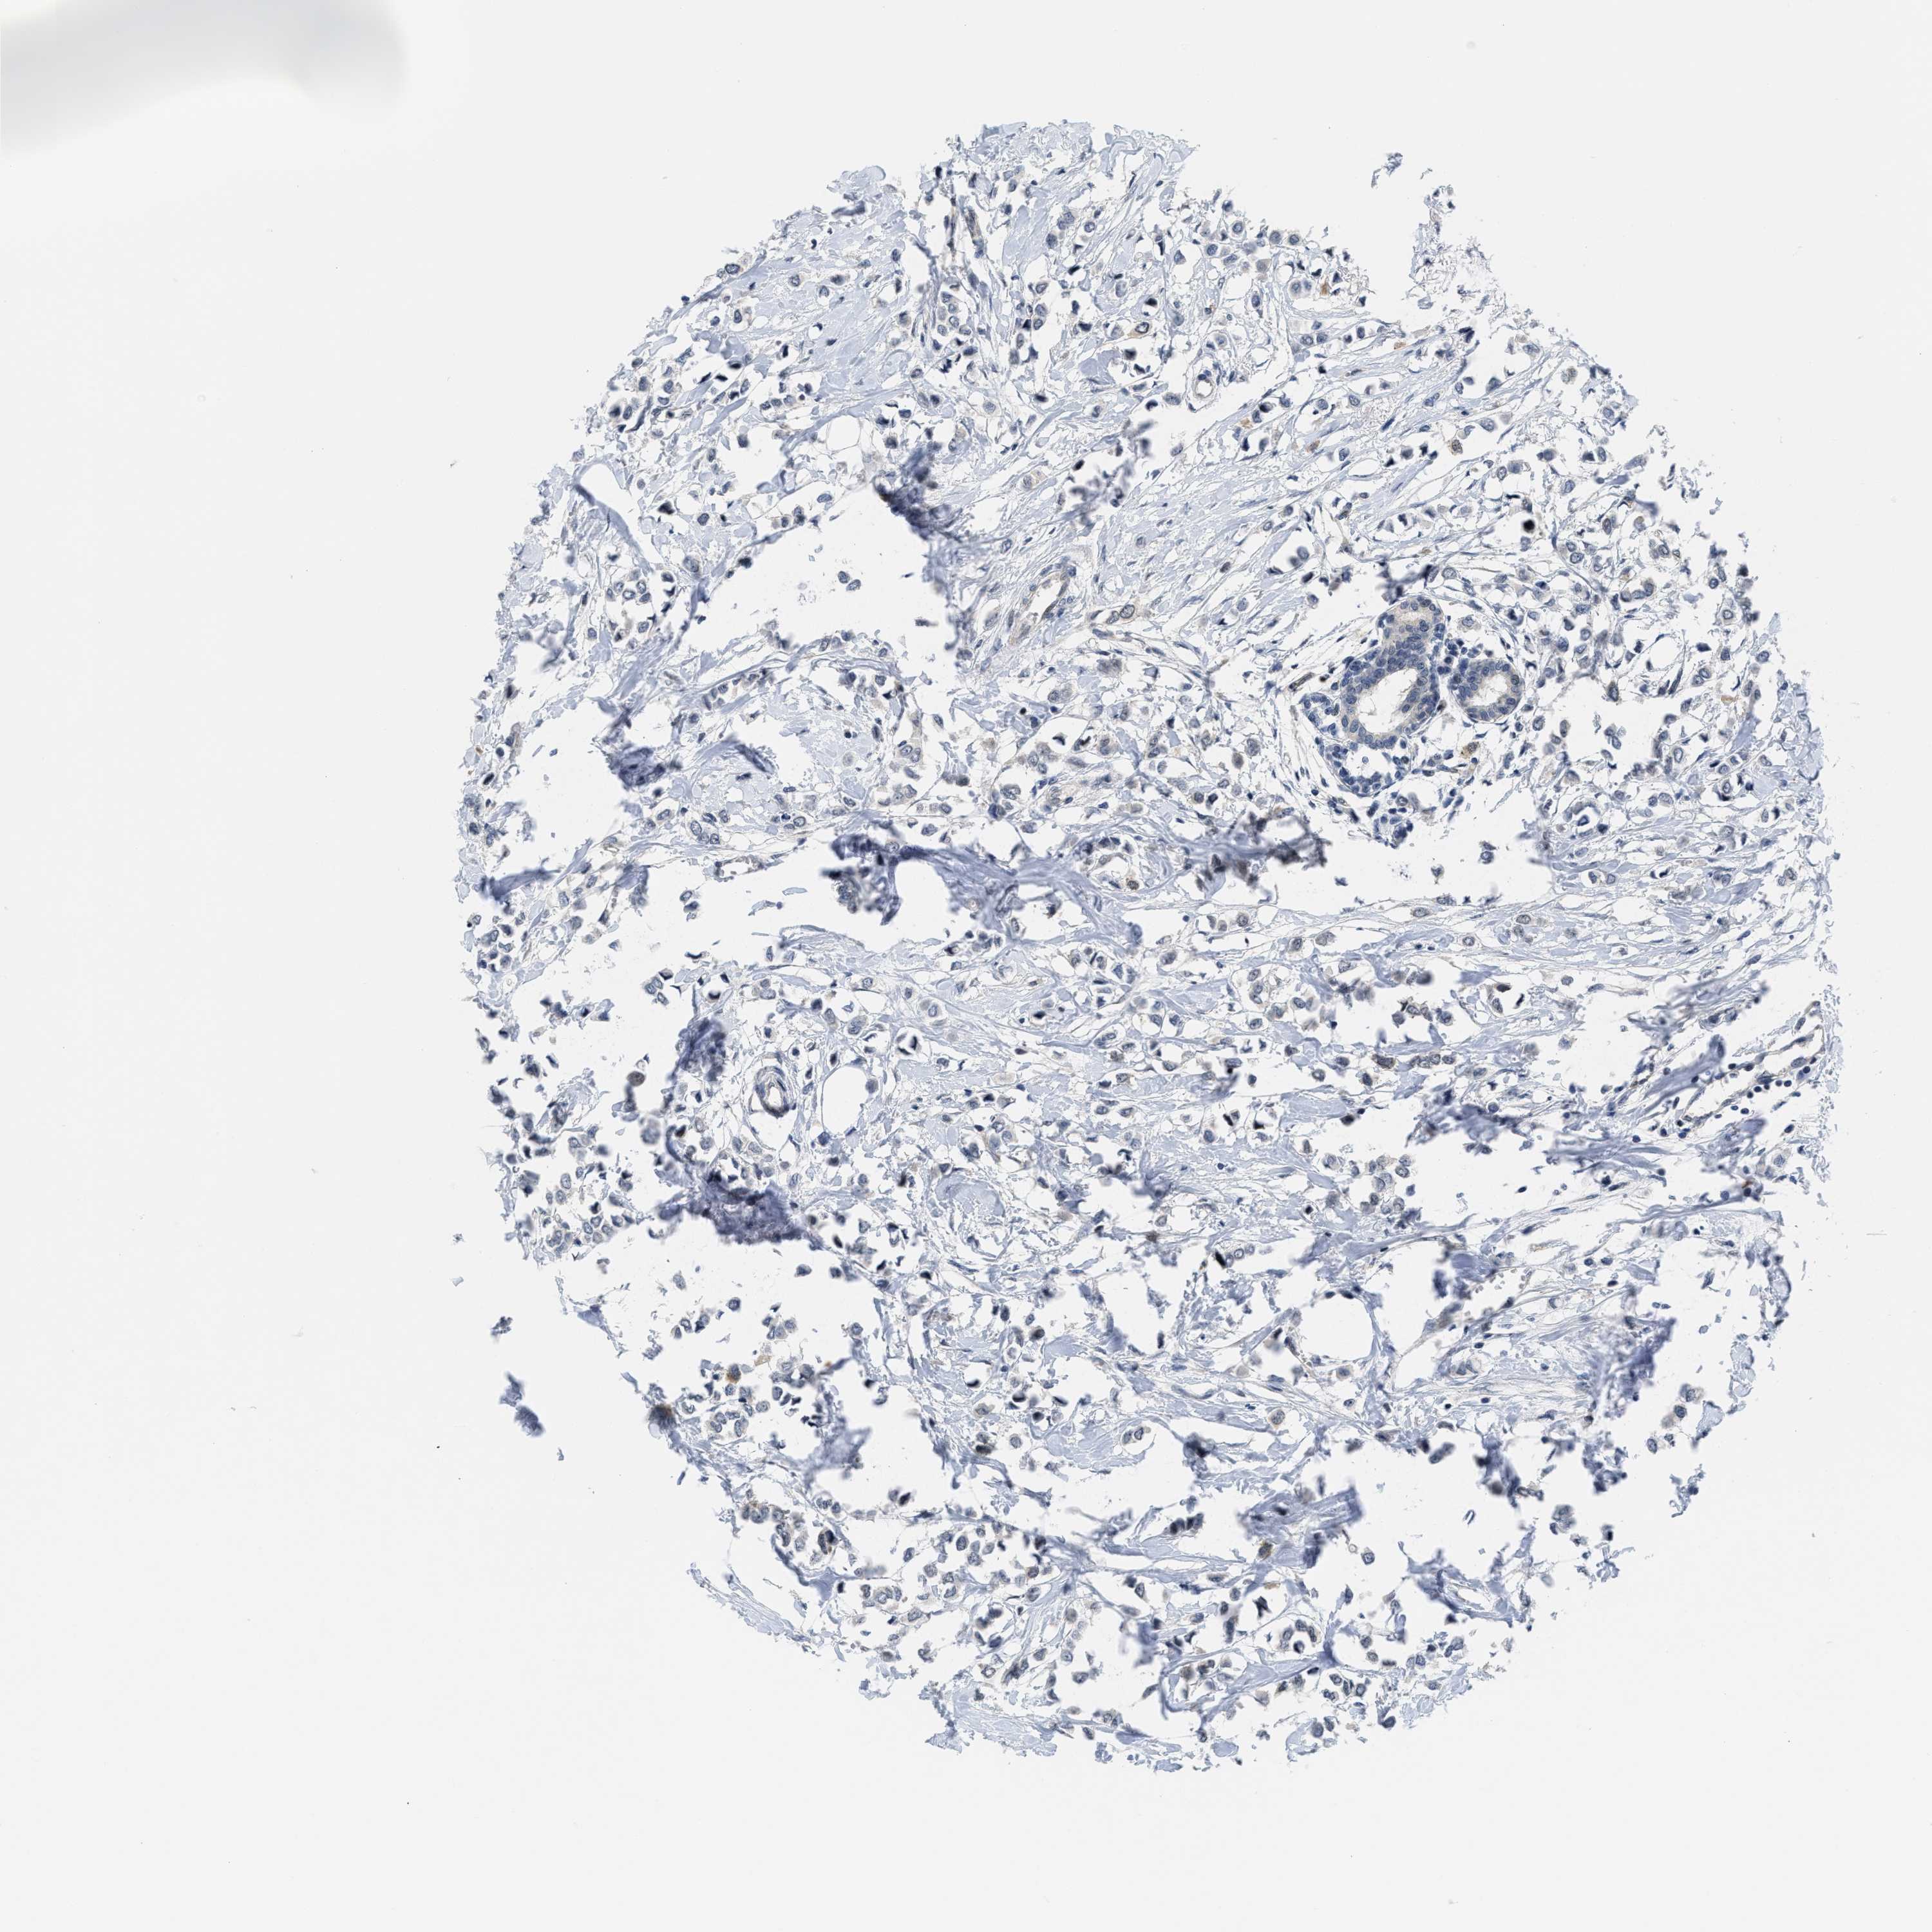

CANCER BREAST CANCER Show tissue menu

BRCA TCGA BRCA VALIDATION PROTEIN EXPRESSION

ANTIBODIES

AND

VALIDATION